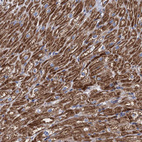

Immunohistochemical staining of human kidney shows strong granular cytoplasmic positivity in cells in tubules.